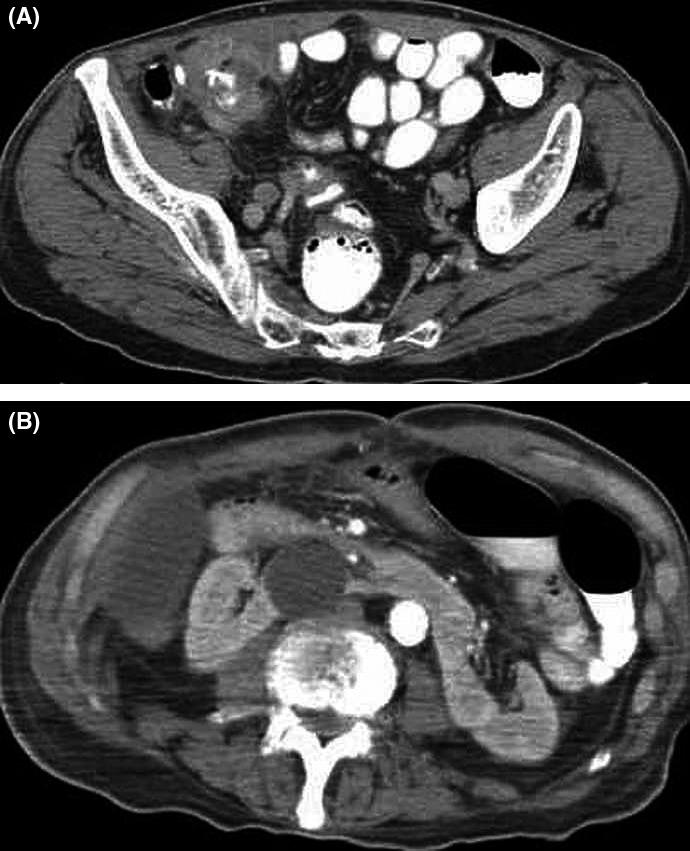

A misdiagnosed cause of early postoperative bowel obstruction.

In the setting of altered anatomy, diagnosis of superior mesenteric artery syndrome requires high clinical and imaging suspicion as the defined imaging criteria cannot be applied.